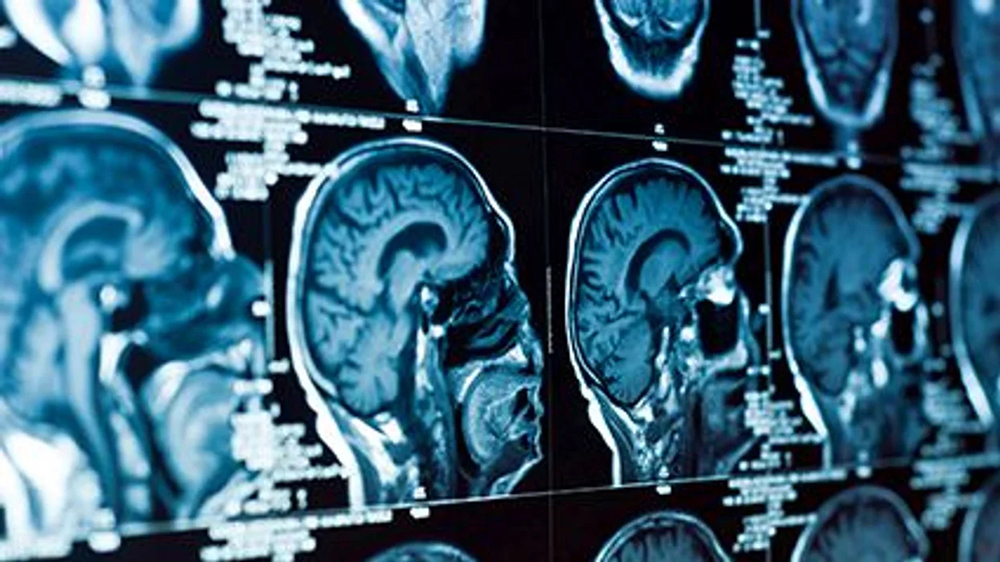

Also, the participants had MRI brain scans to look for enlarged perivascular spaces in two key areas of the brain at the start of the study and every two years for eight years.